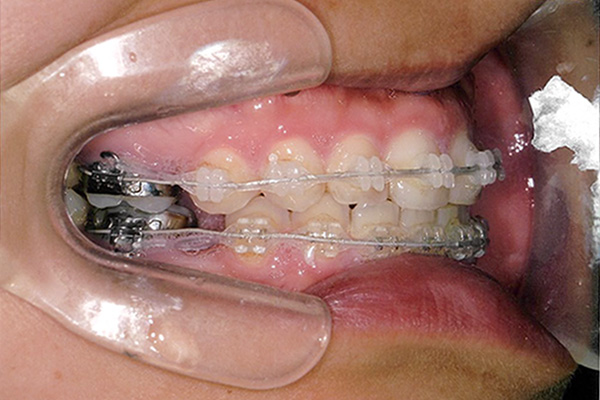

3ヶ月後

10ヶ月後

24ヶ月後

42ヶ月後